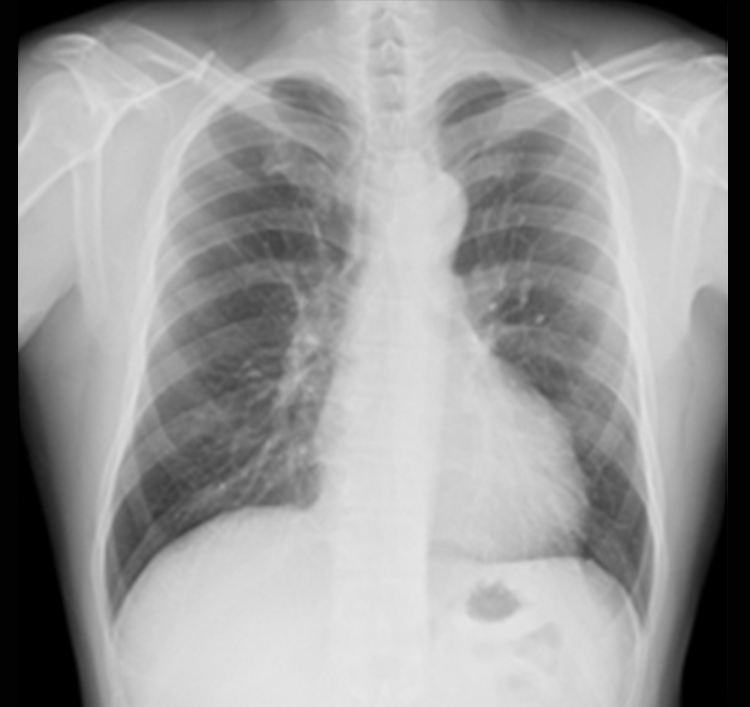

| 検査の特長 肺や気管支などの呼吸器のほか、心臓や縦隔、胸膜などの病変を調べることができます。検査は、胸部X線診断装置に胸部をあて、息を深く吸って止めた状態でX線を照射して撮影します。 |